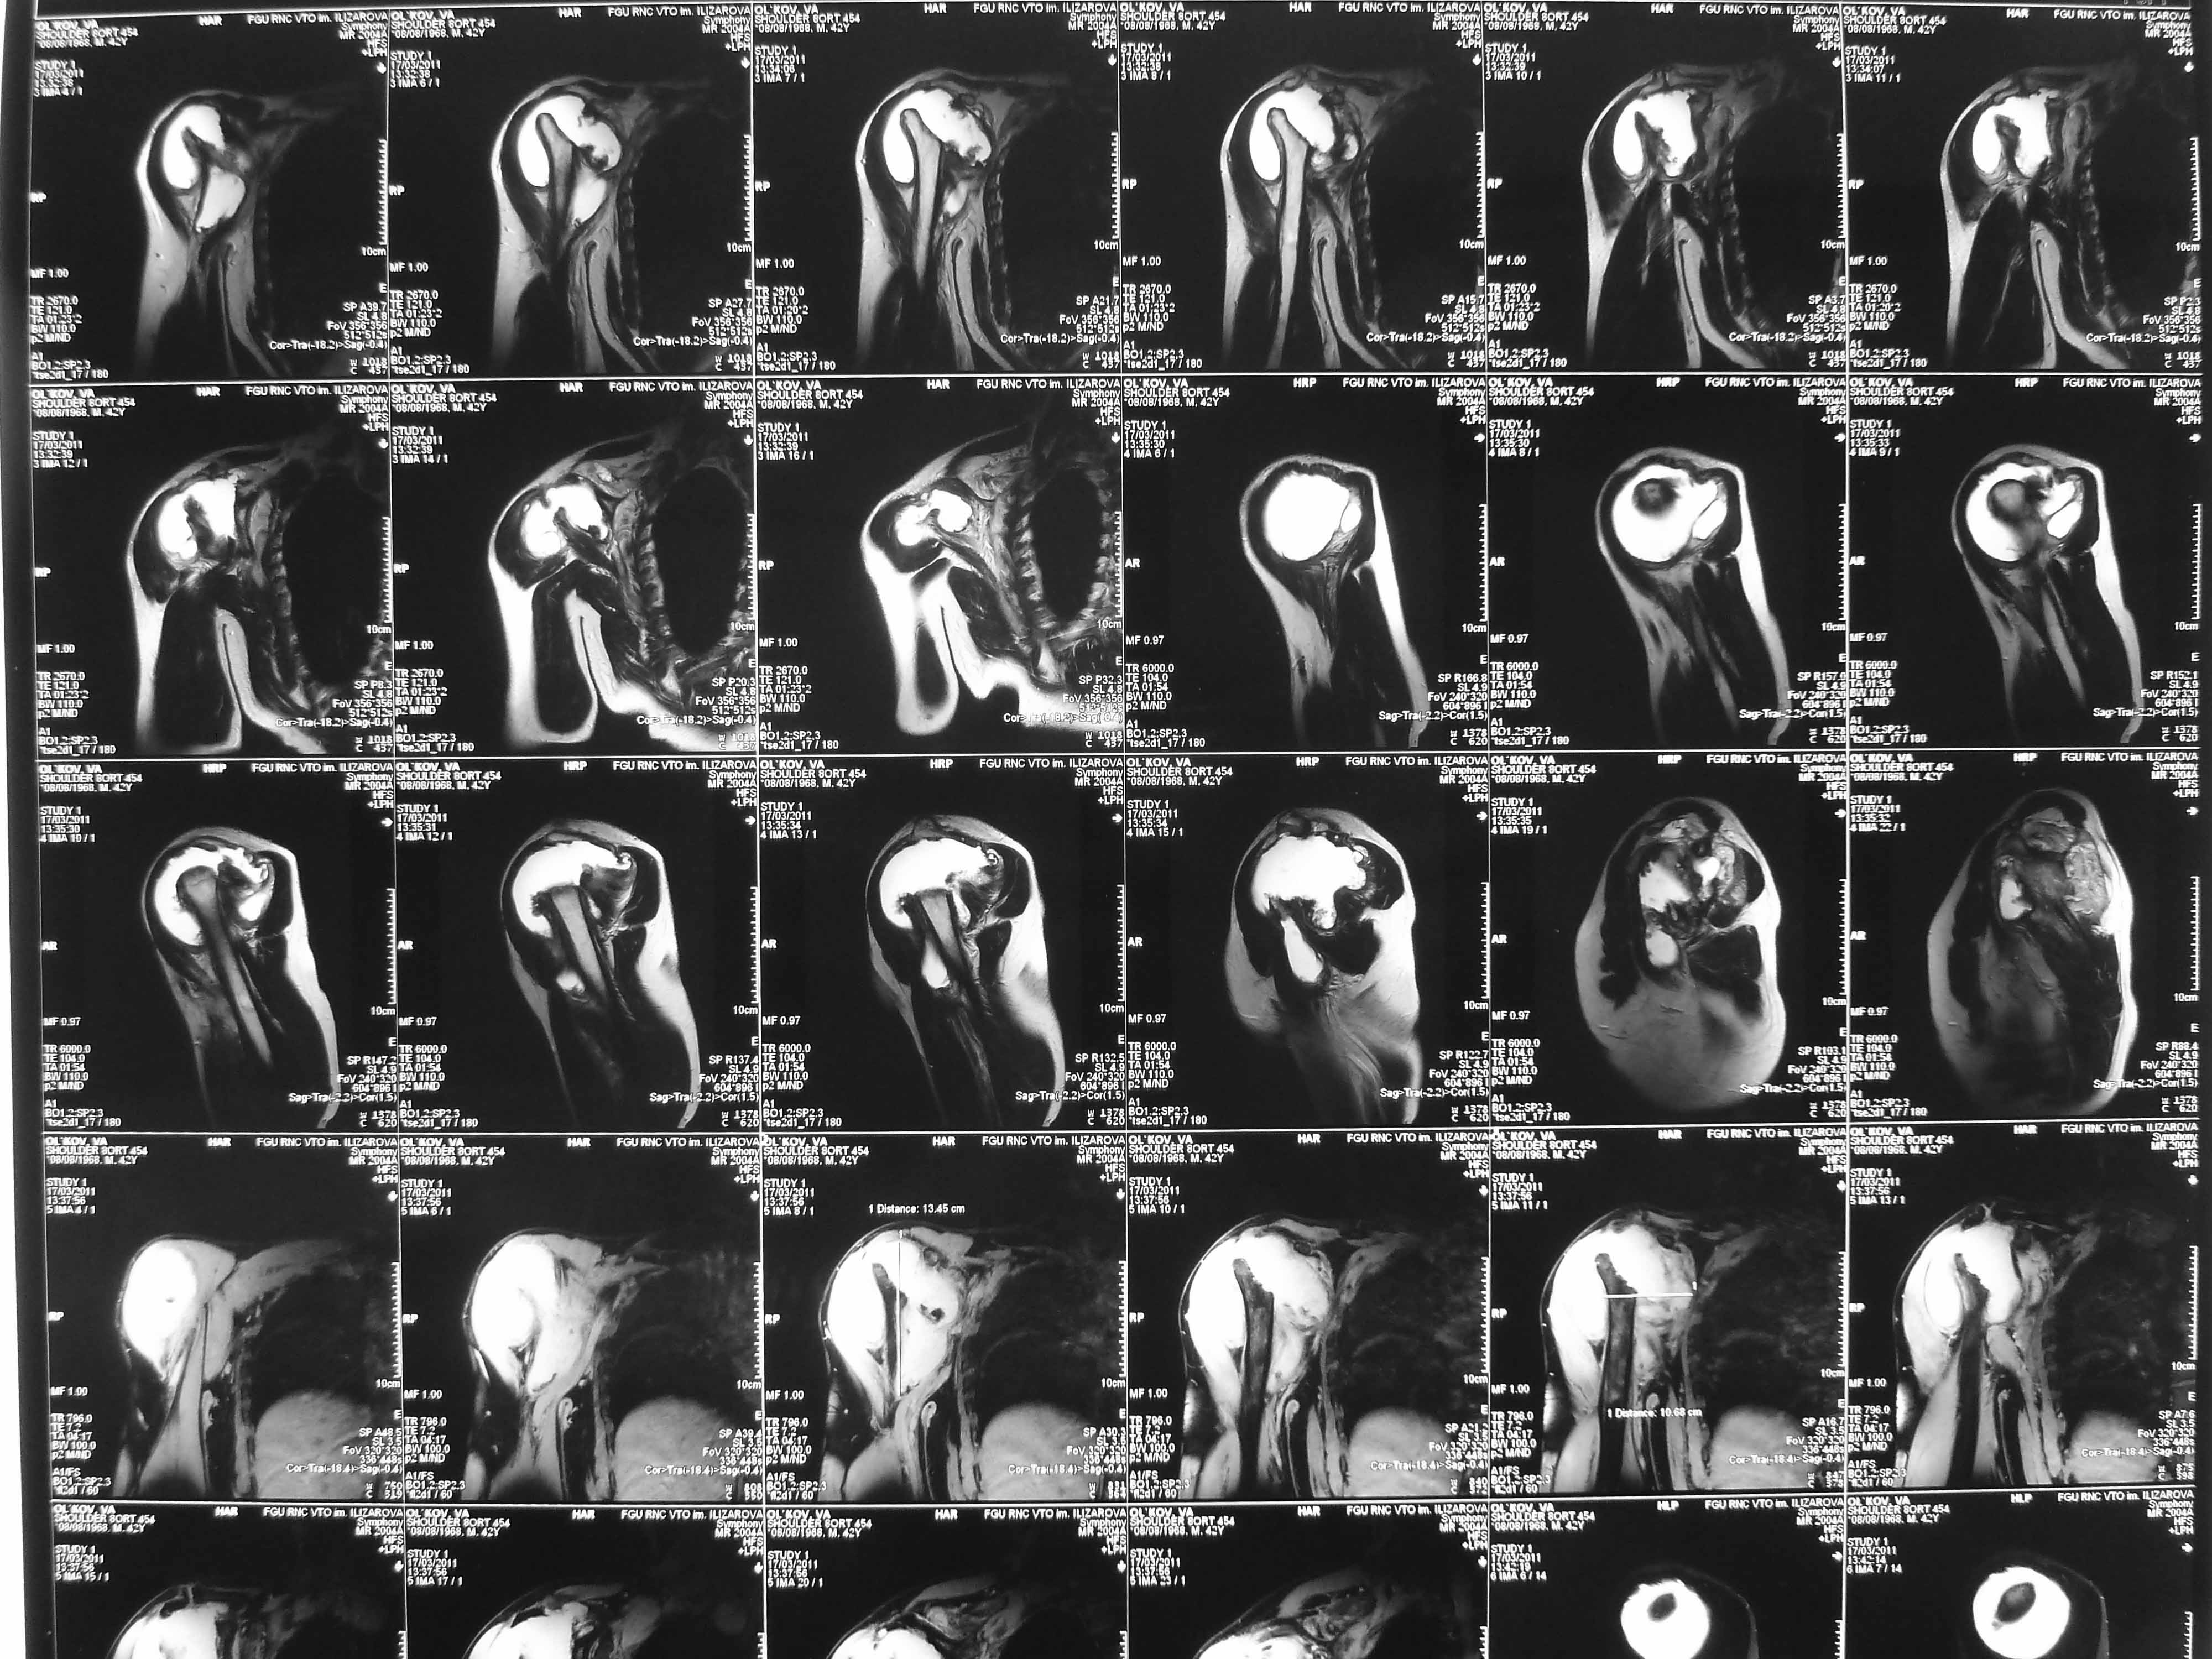

Не усмотрел в анамнезе "ноябре 2009 - травма с потерей сознания. В феврале 2010 г - первый рентген правого плечевого сутава - перелом анатомитеской шейки".

Поэтому желательно выставить все рентгенологические и данные МРТ для сравнения со снимками из статьи.

Думаю, коллеги будут не против увидеть рентген.

Извиняюсь, что-то фотографии сразу не прошли. сейчас исправимся.

Все таки мы решили, что это посттравматичкский аваскулярный некроз. Принято волевое решение выполнить гемиартропластику. На операции: выраженная гипертрофия стенок субакромиальной бурсы. Она была раздута, на операции произведено ее вскрытие, эвакуировано 450 мл суставной геморрагической жидкости. По возможности бурса максимально иссечена, хотели промыть спиртовым расствором хлоргексидина, но побоялись. Вращ манжета - остатки ее найдены в задних отделах сустава, прикрепленные к большому бугорку. малого бугорка и сухожилия подлопаточной мышцы найдено на месте не было. нашли конечно, что-то похожее на сухожилие подлопаточной мышцы и пришили к кости, но я до конца не уверен. полость была дренирована. Сегодня 3 сут после операции - сустав отечен, из дренажа за сутки выделяется около 250 мл геморрагической жидкости. Однако это уже меньше чем в первые дни. Получает НПВС: нимулид по 1т 2 раза и диклофенак 1,0 в/м в сут. Вне зависимости от исхода, постараюсь рассказать об этом в следующих сообщениях. У кого есть мысли по этому, буду очень рад.